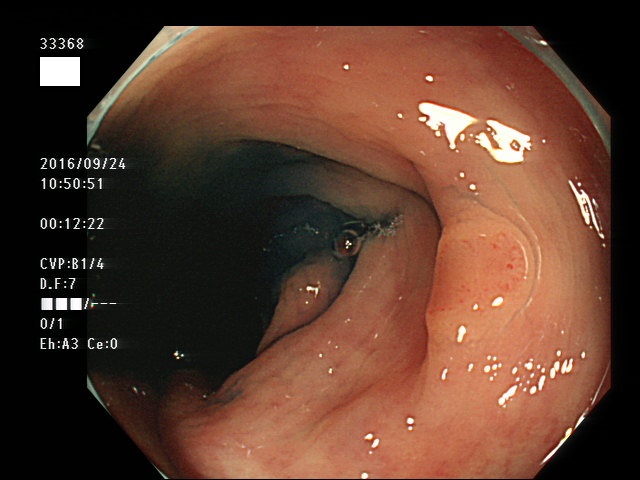

上記100名より抽出した平坦・陥凹型腺腫(=癌化の危険が高いが見落としやすい病変)の内視鏡写真